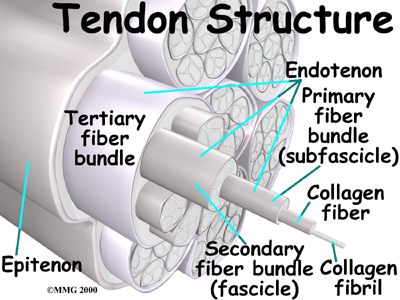

Tendons are made up of strands of a material called . The collagen strands are lined up in bundles next to each other.

Because the collagen strands in tendons are lined up, tendons have high tensile strength. This means they can withstand high forces that pull on both ends of the tendon. When muscles contract, they pull on one end of the tendon. The other end of the tendon pulls on the bone, causing the bone to move.